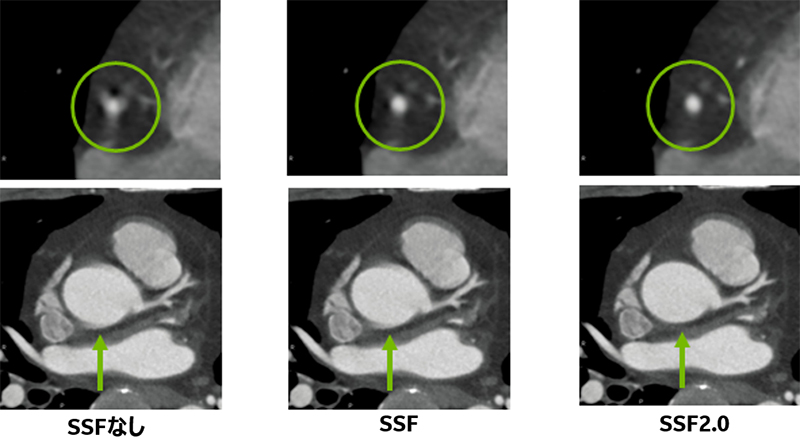

② SSFなし、SSF、SSF2.0 視覚評価

直近20症例において、冠動脈の動きをSSFなし、SSF、SSF2.0でのアキシャル断面で視覚評価を行いました。視覚評価はCT冠動脈解析に携わる放射線技師6名で行い、以下5点満点で評価を行いました(Fig5)。また、20症例の心拍内訳はFig6のとおりです。

Asend_YokohamaSougou_07.jpg

Fig.7 SSFなし、SSF、SSF2.0比較例

評価可能である3点以上がSSFなしでは40%、SSFで70%、SSF2.0で85%となりました(Fig8)。

また、心拍別で比較した場合、60BPM以下におけるSSFなし、SSF、SSF2.0の差はそれほどみられませんでしたが(Fig9 赤枠)、従来静止した冠動脈の描出が難しかった70BPM付近において、SSFやSSF2.0では改善がみられ、特にSSF2.0ではその効果が顕著にみられました(Fig9 黄枠)。

さらに、70BPM以上ではSSFでも大幅な改善が難しく、SSF2.0のみ大きな改善がみられました (Fig9 青枠)。